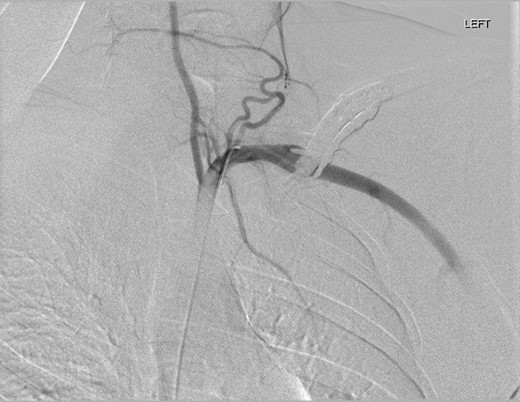

On examination, there was an obvious pulsatile mass posterior to the left clavicle. The perpendicular plates were palpable, with prominent screws. At the time, all upper limb pulses were present with no signs of embolic disease. Neurological examination was also unremarkable. A recent Doppler ultrasound suggested that a plate fixation screw was impinging on the subclavian artery wall, causing increased wall thickness. Computer tomographic angiography (CTA) depicted a left subclavian artery pseudoaneurysm, yet there was significant metalware artefact. Thus, digital subtraction angiography (DSA) was booked (Figures 1 and 2). Yet, prior to undergoing this, he was admitted with sudden worsening of left arm pain and paraesthesia associated with movement despite a viable arm with present distal pulses.

DSA oblique view illustrating fusiform left subclavian pseudoaneurysm.

Digital subtraction angiography via the right common femoral artery (CFA) was performed depicting fusiform aneurysmal dilatation of the mid left subclavian artery posterior to the clavicular plates and screws. Further, a focal area of irregularity was noted along the inferior aspect of the artery at the distal aspect of the aneurysm. On the dynamic study with arm in abduction there was significant compression of the artery by prominent clavicular screws at the site of the pseudoaneurysm.